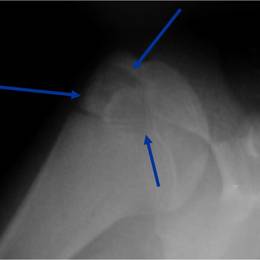

Radiographic imaging is used to help form a diagnosis of Chondroblastoma. Scans include X-Ray, MRI and Bone Scan. CT scan is sometimes used to assess the adjacent bone quality and look for flecks of calcium in the tumor to aid in diagnosis. MRI usually shows extensive swelling around the tumor that is sometimes misinterpreted as a cancer.

An example of a Chondrosarcoma X-Ray.